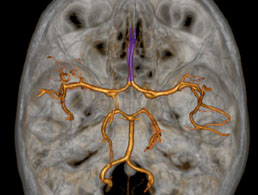

- Polygone de Willis

- Veines de l'encéphale

- Carotide externe